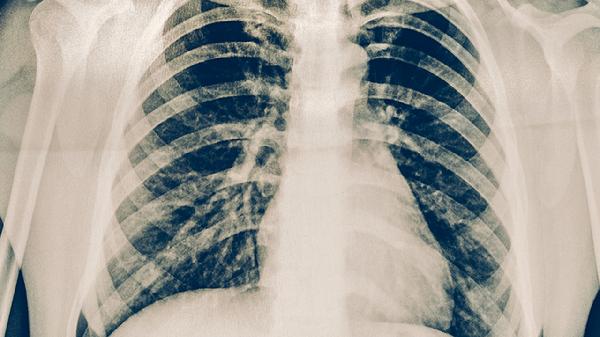

結(jié)核病密切接觸者、HIV感染者、糖尿病患者等高危人群應(yīng)定期進(jìn)行胸部X線或結(jié)核菌素試驗(yàn)檢查。出現(xiàn)咳嗽、低熱、盜汗等可疑癥狀超過(guò)2周時(shí)需及時(shí)就醫(yī)。醫(yī)務(wù)人員應(yīng)每年進(jìn)行職業(yè)健康檢查,早期發(fā)現(xiàn)潛伏結(jié)核感染。